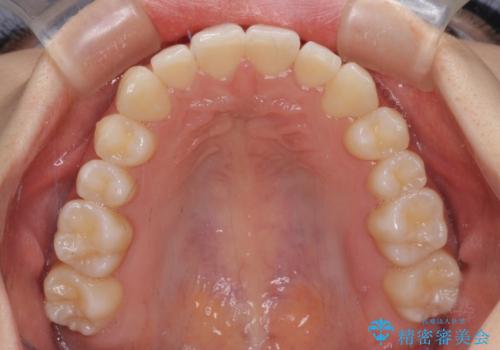

前歯のクロスバイト インビザラインによる矯正治療

- 前歯のクロスバイトを気にして来院された患者様です。

短期間での治療を希望され、ワイヤー装置とインビザラインとで悩んでいましたが、自己管理を徹底すると言うことでインビザラインによる矯正治療を行うこととしました。

しっかりとインビザラインの装着時間を守っていただいたので、1年弱で矯正治療を終えることができました。